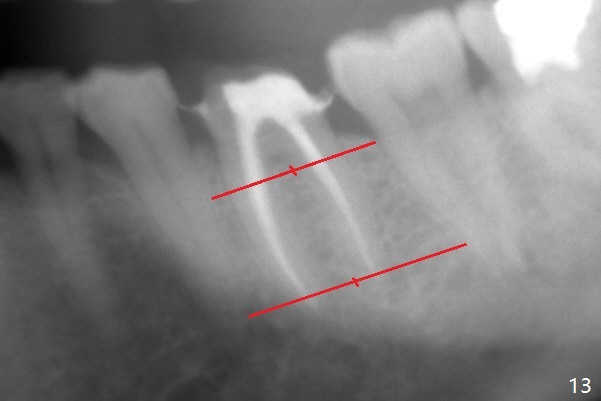

When the patient returns 9 months later, there is severe buccal gingival recession and abscess at #19 (Fig.1 *) with large mesial periradicular radiolucency (Fig.2 *). The septum is thin and the buccal crest is low after extraction (Fig.3 * (mesial root vertical fracture)). Osteotomy is initiated in the mesial socket immediately against the septum (Fig.4.5) with ~ 5 mm in the native bone. Due to severe buccal plate resorption, a shorter implant is placed (Fig.6; 5x15 mm in stead of 18 mm). There is at least 2 mm gap buccally for Vanilla Graft, which is also placed next to the implant and the neighboring root (Fig.7 *). There is clearance from the Inferior Alveolar Canal (Fig.8 red dashed line). Both the mesial and distal sockets heal 5.5 months postop (Fig.9), although the apical portion of the distal socket was not filled with allograft (Fig.7). The implant was placed mesial. The straight abutment (6.5x4(4) mm) (Fig.10) is changed to an angled one (5.5 x15 degrees 3 mm cuff (Fig.11)) before impression. The implant is also placed buccally. Therefore the implant position is far more important than its length. The abutment is retightened 2.5 months post cementation, which is related to mesiobuccal placement of the implant (Fig.12). An ideal trajectory is determined by drawing 2 horizontal lines (at crestal and apical levels: red lines in Fig.13), finding a central point of each line (vertical short line) and joining these 2 central points (Fig.14 pink line). In fact the ideal osteotomy should have been established distal to the septum in this case. Guided surgery may alleviate the issue. The crown is not loose, but the patient feels that the implant tooth cannot sustain mastication. In fact the screw is removed with hand driver (not wrench). The abutment hex is rounded and worn. A new 5.5x4(4) mm abutment is placed (without knowledge of previous use of an angled abutment) with mesial reduction to reduce undercut and buccodistal margin lowered to reduce gingival embrasure. It is that the straight abutment could decrease the chance of screw loosening. Otherwise the implant has to be removed for better trajectory.